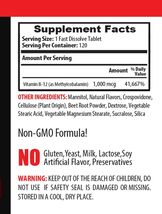

METHYLCOBALAMIN VITAMIN B12

ENERGY PROMOTING VITAMIN

ENHANCES FUNCTIONAL COGNITION

PROMOTES HEALTHY MOODS

HEART HEALTH SUPPORTER

GUT HEALTH SUPPORTER

PROMOTES SKIN AND HAIR HEALTH

CAN PROMOTE SOUNDLESS SLEEP

1 BOTTLE = 120 QUICK DISSOLVE TABLETS

METHYLCOBALAMIN B-12: Vitamin B-12 is a water soluble vitamin that has many important system functions in humans. It is integral to DNA production, cardiovascular support, and energy metabolism. In this post, learn more about the crucial Vitamin B12, its functions, as well as the benefits it can provide in your life. This is one of the most popular deficiency vitamins in the world.